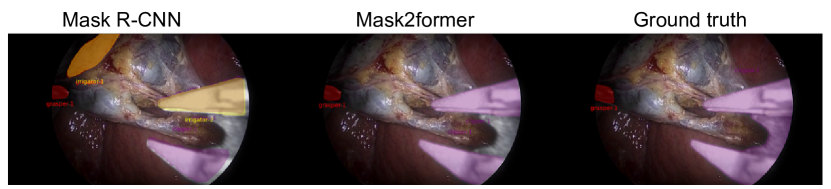

To validate the usability of the CholecInstanceSeg dataset, two baseline instance segmentation models, The Mask R-CNN [20] and the Mask2Former [21] were trained. Since the objective was to establish benchmark performance metrics that future researchers can use for comparison, we decided to utilize more generalizable baseline models instead of optimized tool-specific models like [22, 23]. These models were trained using the training split of CholecInstanceSeg with each model’s default hyperparameters.

Results

The performance results, presented in Table 3, show the effectiveness of the dataset in training robust instance segmentation models. A figure showing the qualitative results of both models against groundtruth for an image from the validation dataset can be seen at Figure 11. A video of more results from both models on the validation dataset can be found here

| Model | val mAP | val smAP |

|---|---|---|

| Mask R-CNN | 0.470 | 0.437 |

| Mask2Former | 0.682 | 0.655 |